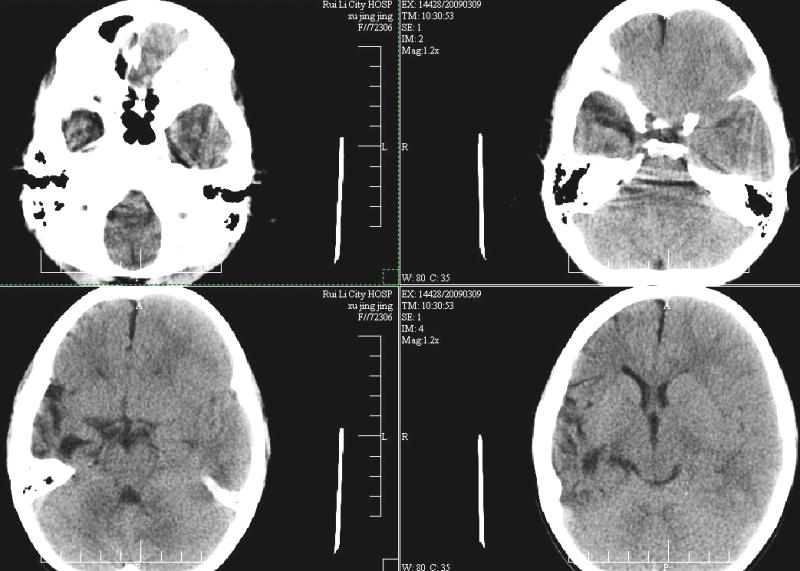

标题: PED1810:F,9岁。头痛,昏倒,一周一次,共半年。 [打印本页]

标题: PED1810:F,9岁。头痛,昏倒,一周一次,共半年。

ct:右顶叶脑软化灶合并右侧大脑半球发育不良可能。

支持大脑发育不全。

支持大脑发育不良

支持右侧大脑发育不良。

右侧大脑发育不良